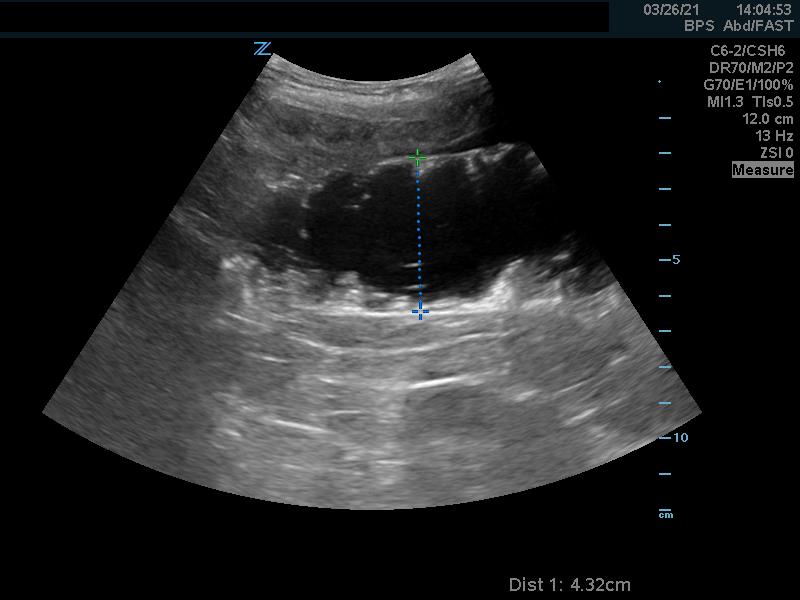

- The intussusception is usually 3-5 cm in diameter and often fills the screen, which makes it easier to diagnosis by point-of-care ultrasound.8

- When the intussusception is seen it should be imaged in both long (Fig. 6a, Video 3) and short (Fig. 6b, Video 3) axis.

- In the long axis, a kidney-shaped mass, which is often called the pseudokidney sign, is seen. This is an oblique view of the invaginated bowel. (Fig. 6a)

- Figure 6a. Image in long axis of ileocolic intussusception